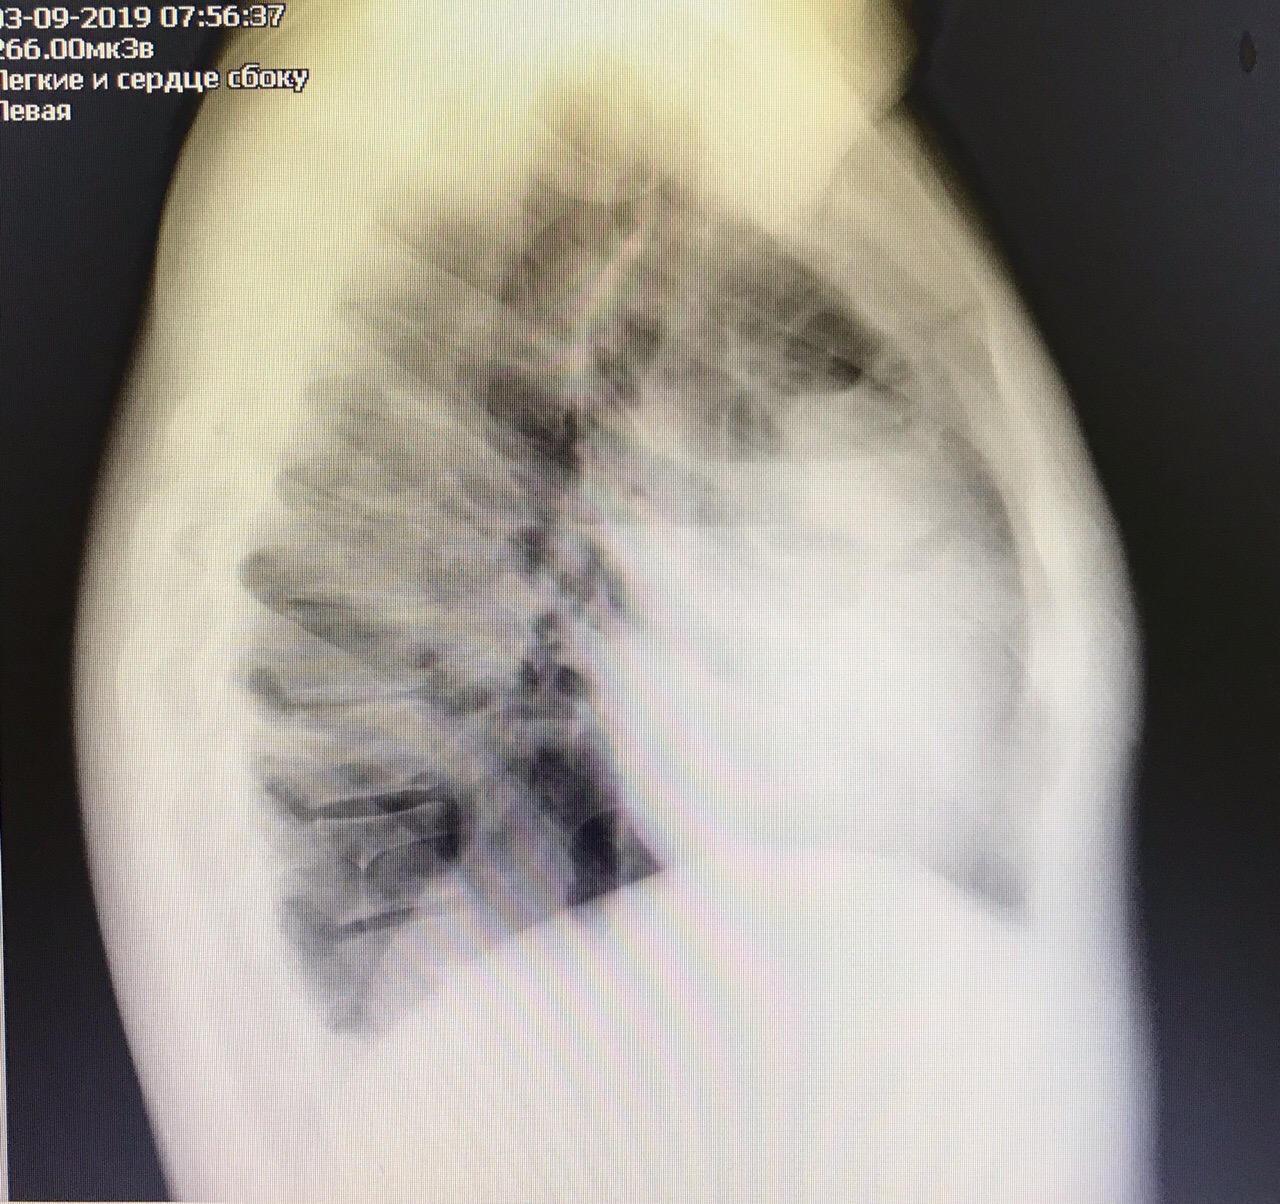

Гидроторакс. Серия снимков.

1 - лежа. Так делать не надо! Надо только сидя!

2 - сидя. Понятно, что гидроторакс за раз не победить

3 - удалено 1100.

4 - удалено ещё 1200. И диуретики все эти дни.

Обсуждалось в ГОспитале Ослабленных Сердец.